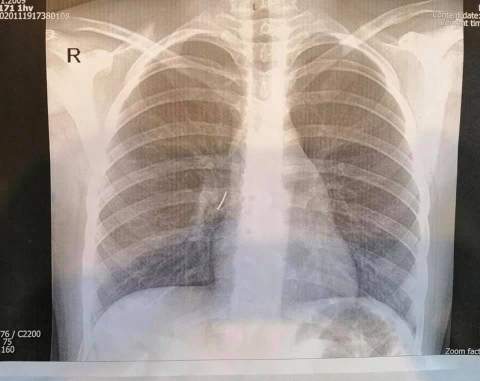

Рентген показав, що у дитини в бронхах чужорідне тіло, після чого хірург Олександр Колодій провів термінову операцію.

Втручання було дуже складним, адже діаметр трахеї дитини всього 8 мм і працювати там щипцями непросто. Завжди є високий ризик профузної кровотечі, що може призвести до смерті дитини. На щастя, цвях вдалося вийняти без ускладнень.

"Ми зробили рігідну трахеобронхоскопію під наркозом. Спеціальними ендоскопічними інструментами - щипцями під оптичним контролем - з правого проміжного бронха дитини ми отримали канцелярський цвях з пластмасовою частиною і гострим вістрям. Це було непросто, адже пластмасова частина цвяха повністю перекрила бронх так, що нижня частка правої легені майже не функціонувала", - говорить хірург.